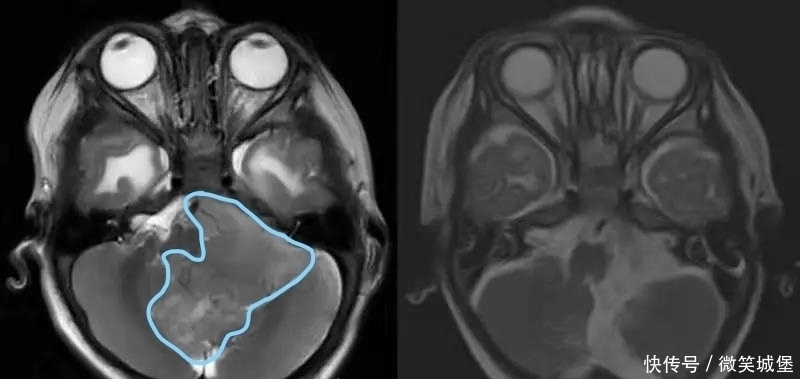

术中可见一个65*54*60mm肿瘤自四脑室正中孔突出,进入枕骨大孔以下,压迫延髓及颈髓。专家在切除肿瘤的同时,注意小心保护相关的神经和血管结构。

经过3个半小时的显微操作,手术将肿瘤全部切除。